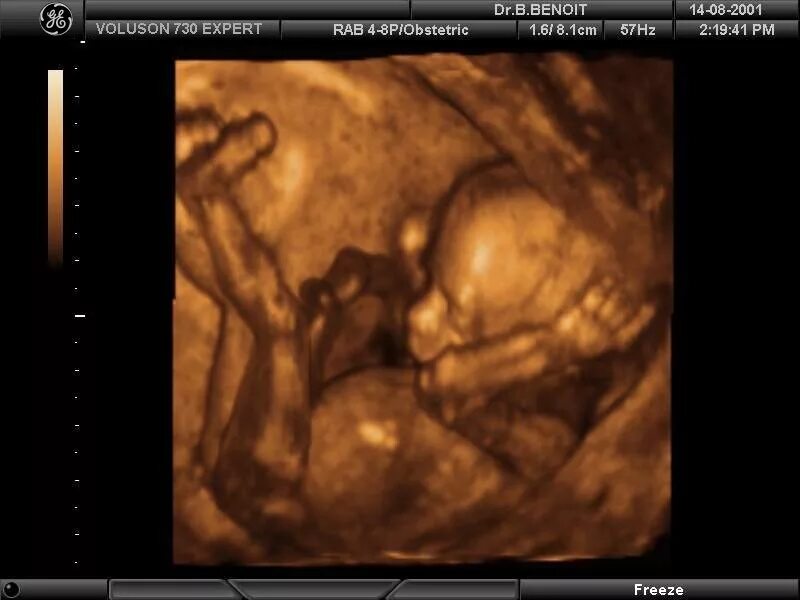

Как выглядит 16 неделя беременности фото